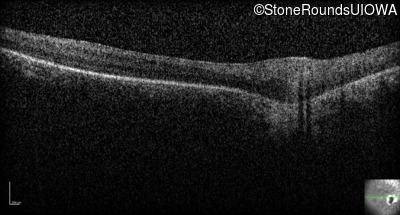

Optical Coherence Tomography - Right - Light Perception

Exemplar / OCT Stack

Optical Coherence Tomography - Left - Light Perception